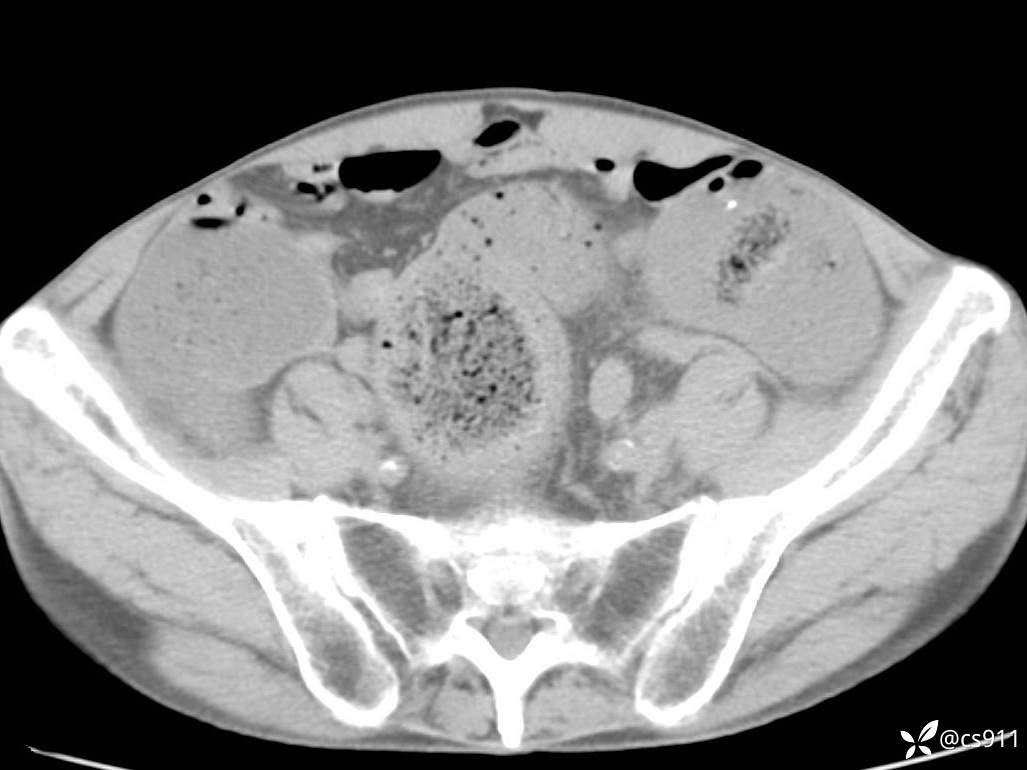

急腹症之急诊CT,原因?答案公布

男,77岁,腹痛、腹胀伴恶心呕吐1天。呕吐胃内容物,非喷射性呕吐,有咖啡色样胃内容物,诉有胃穿孔病史。查体:全腹平,下腹部压痛,全腹无反跳痛,叩诊呈浊音,移动性浊音阴性,肠鸣音减弱,1-2次/分。肛检:直肠未扪及明显肿物,可触及大量粪块。

T 36.6℃ P 80次/分 R 26次/分 BP 100/60mmHg

白细胞(WBC) H 14.55 10e9/L 4-10

中性粒细胞百分率(NEUT%) H 85.7 % 40-75

血淀粉酶(AMY) HH 1859 U/L 35-135

癌胚抗原(CEA) H 27.44 ng/ml 0-5

呕吐物 潜血试验 * 阳性 阴性

患者轮椅入室检查神志清楚, 能配合摆位和呼吸